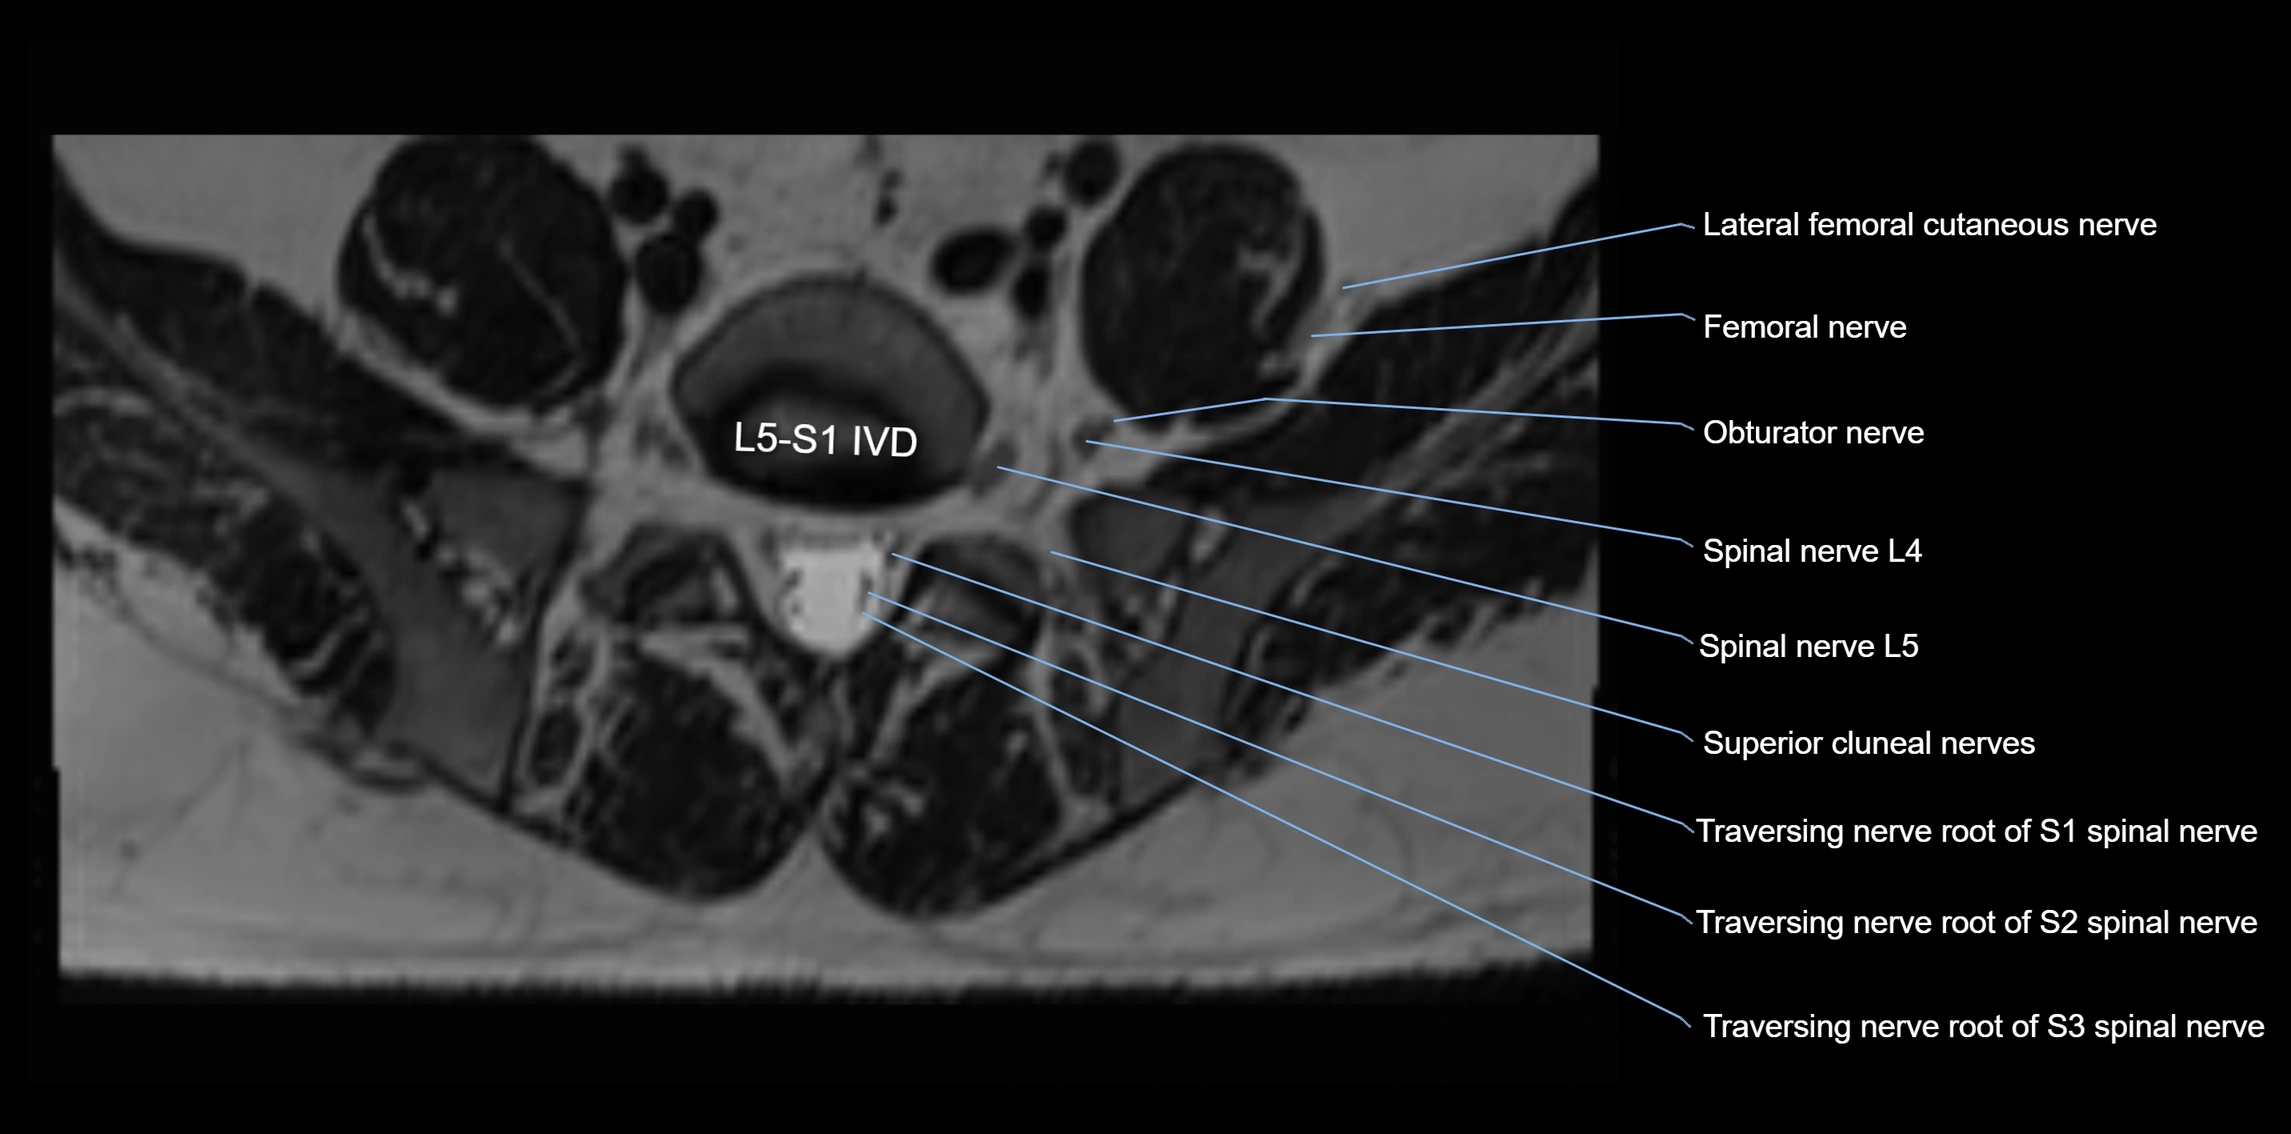

MRI image

image